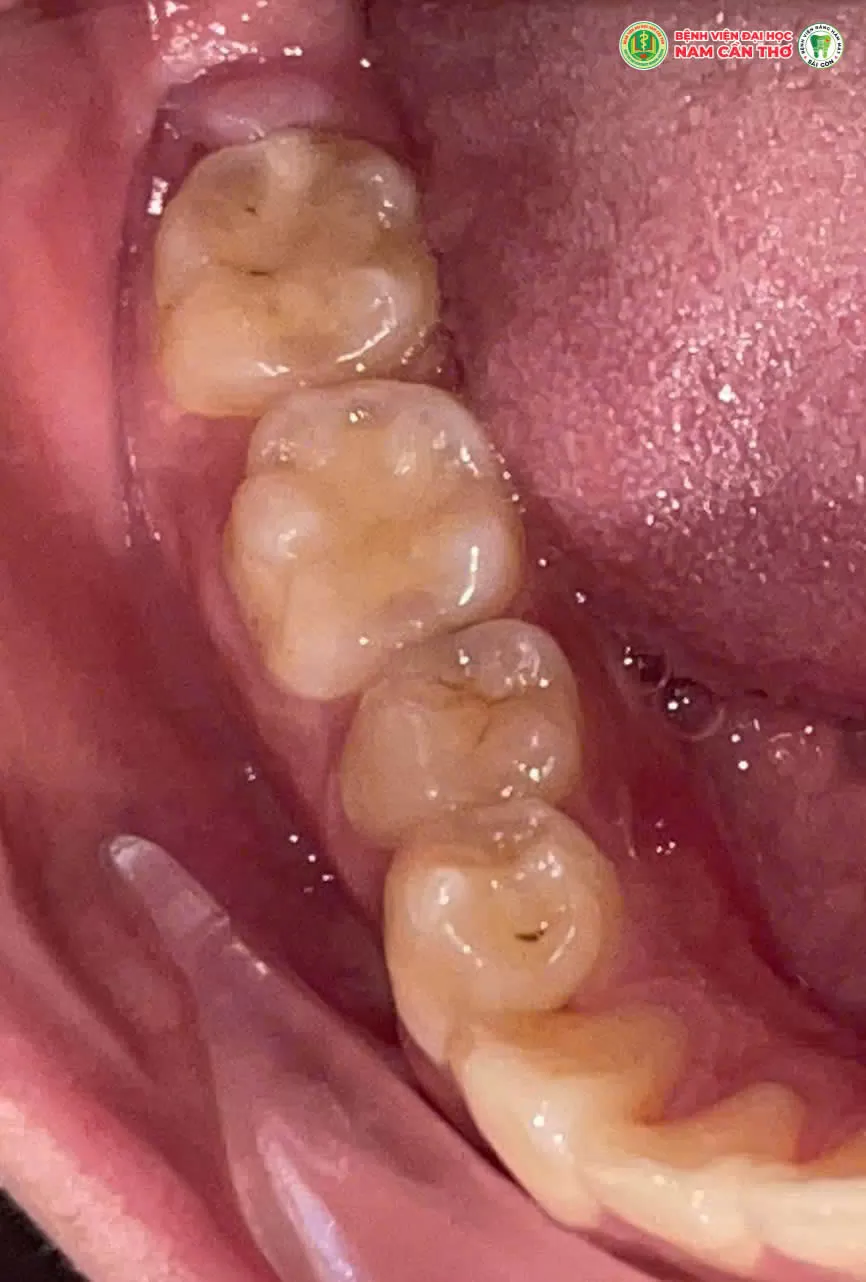

✨Răng khôn thường mọc lệch, mọc ngầm hoặc chen chúc gây đau nhức viêm nhiễm và ảnh hưởng đến các răng bên cạnh. Việc nhổ răng khôn đúng thời điểm đúng kỹ thuật là cần thiết để đảm bảo sức khỏe răng miệng lâu dài.